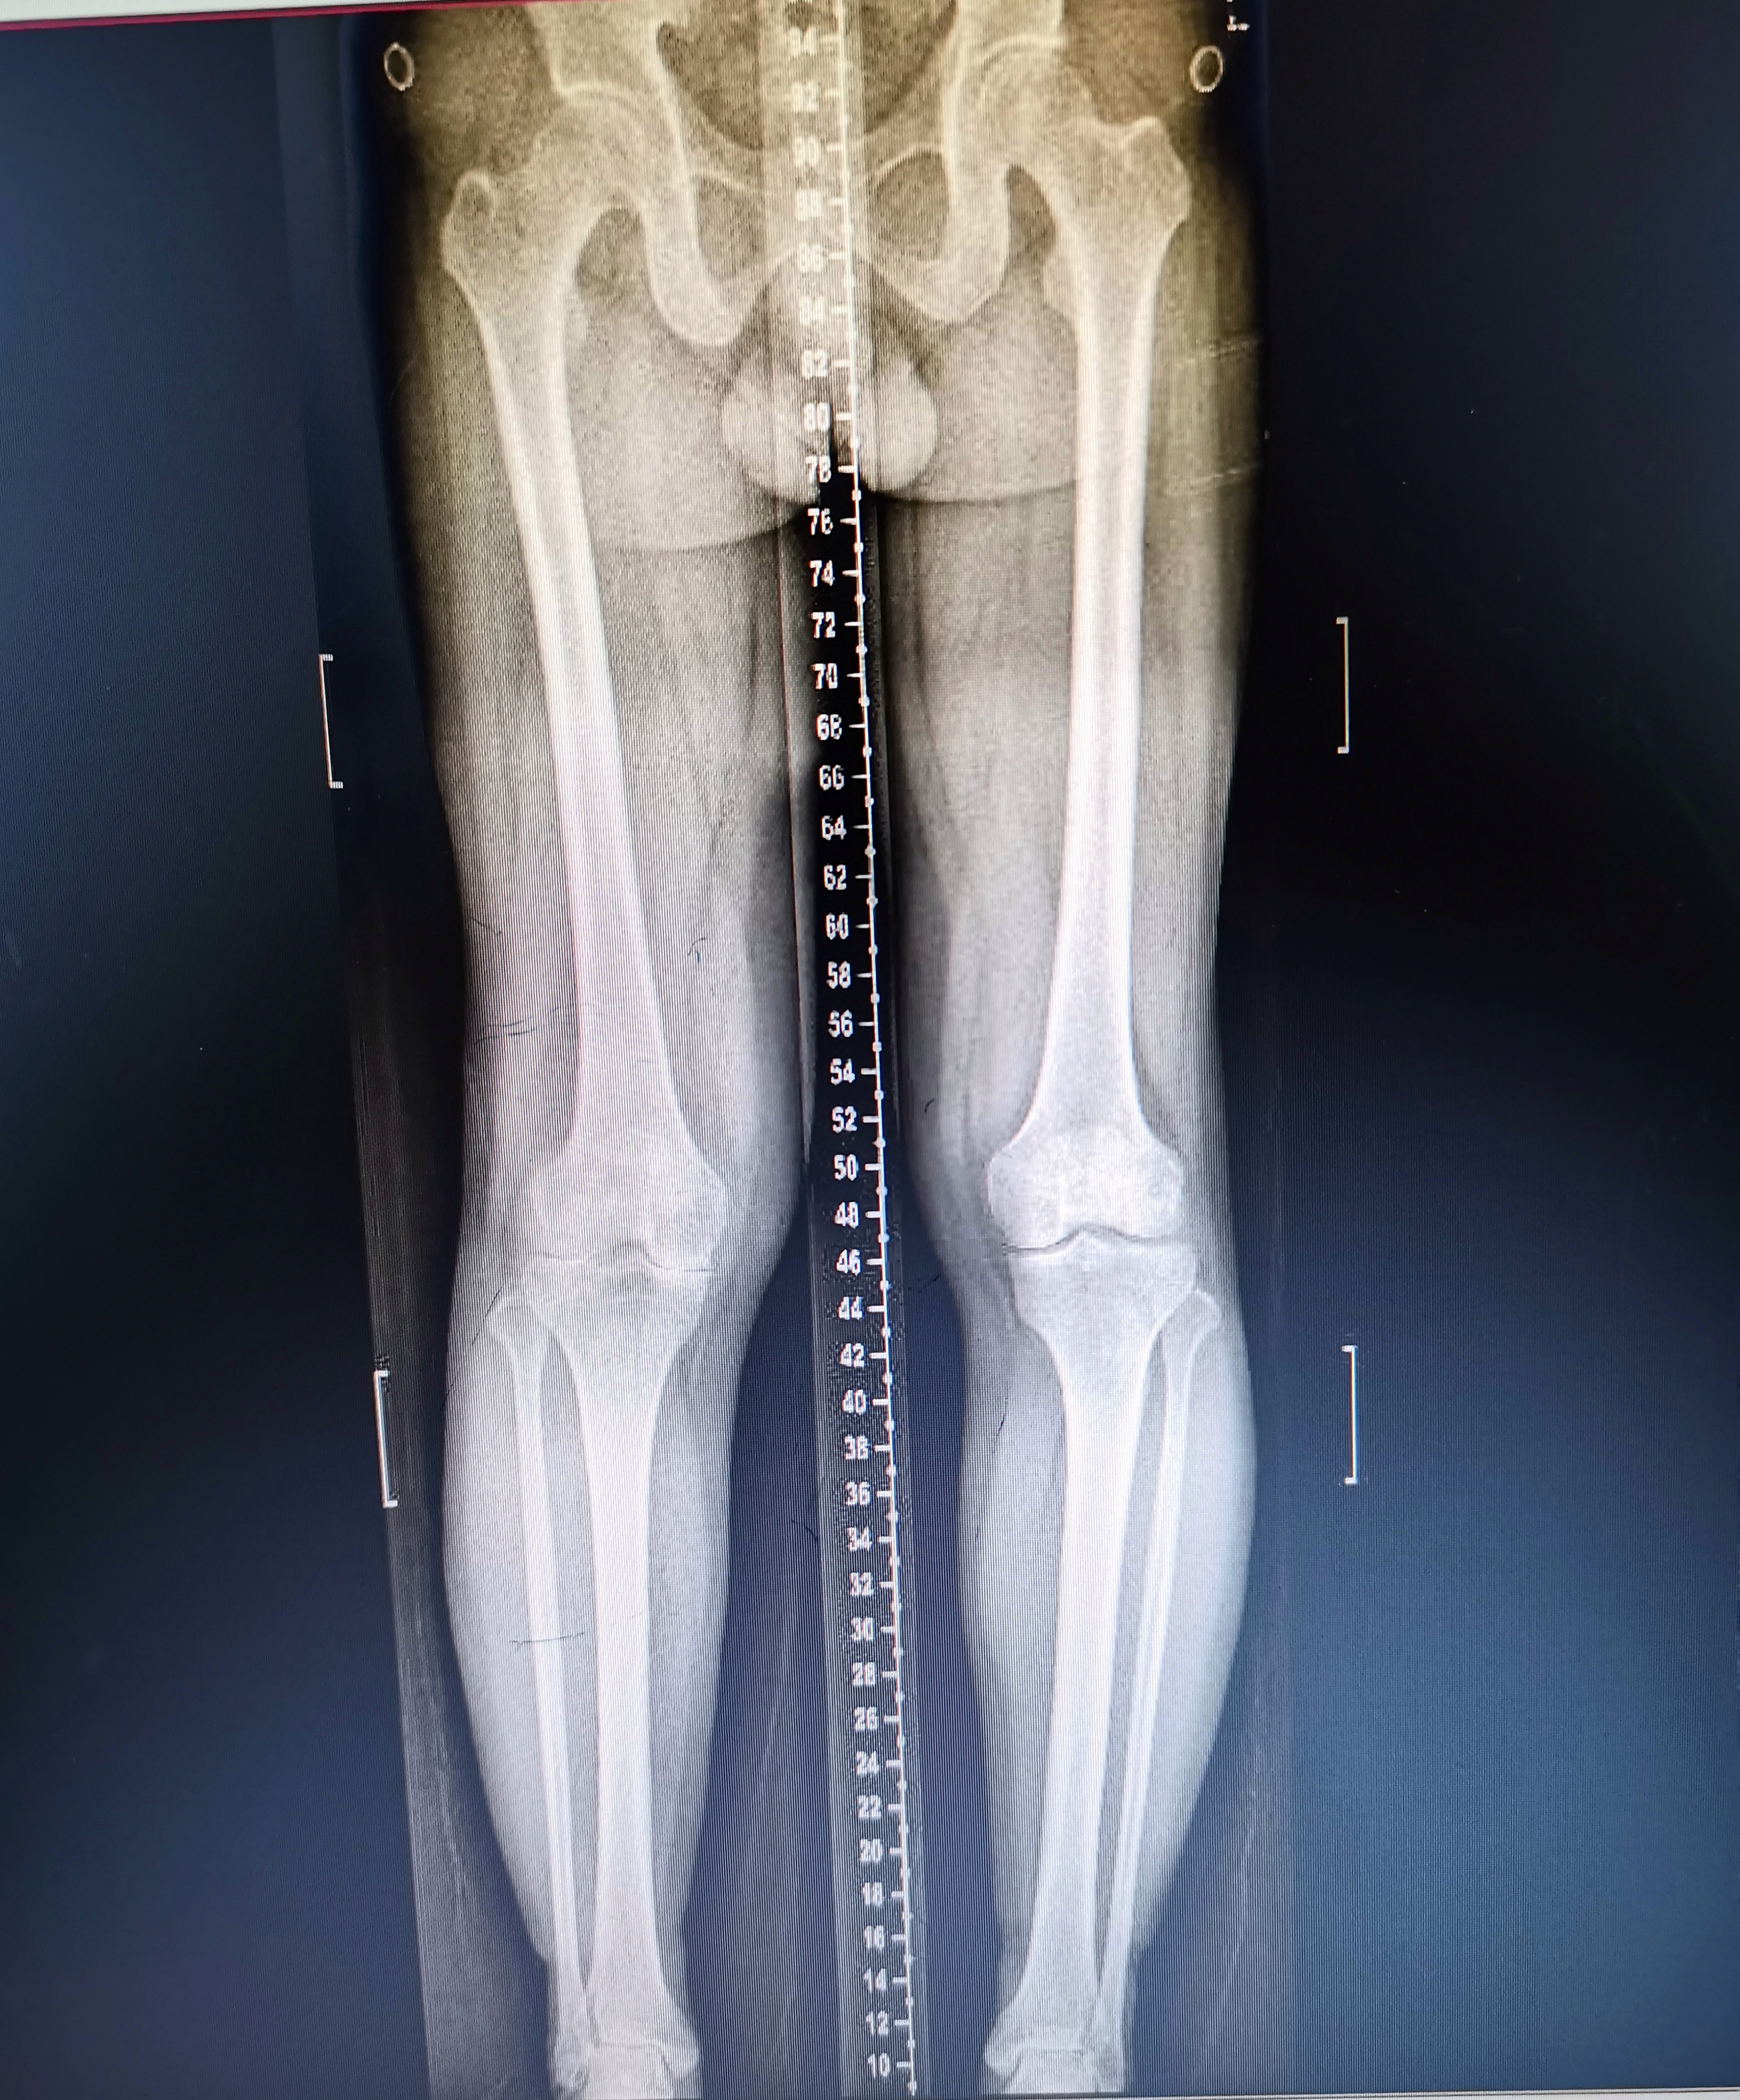

患者情況基本情況:男性,53歲

主訴:雙膝關節疼痛4年,加重3月。

初步診斷:1雙側膝關節骨性關節炎

2類風濕性關節炎

術前照片